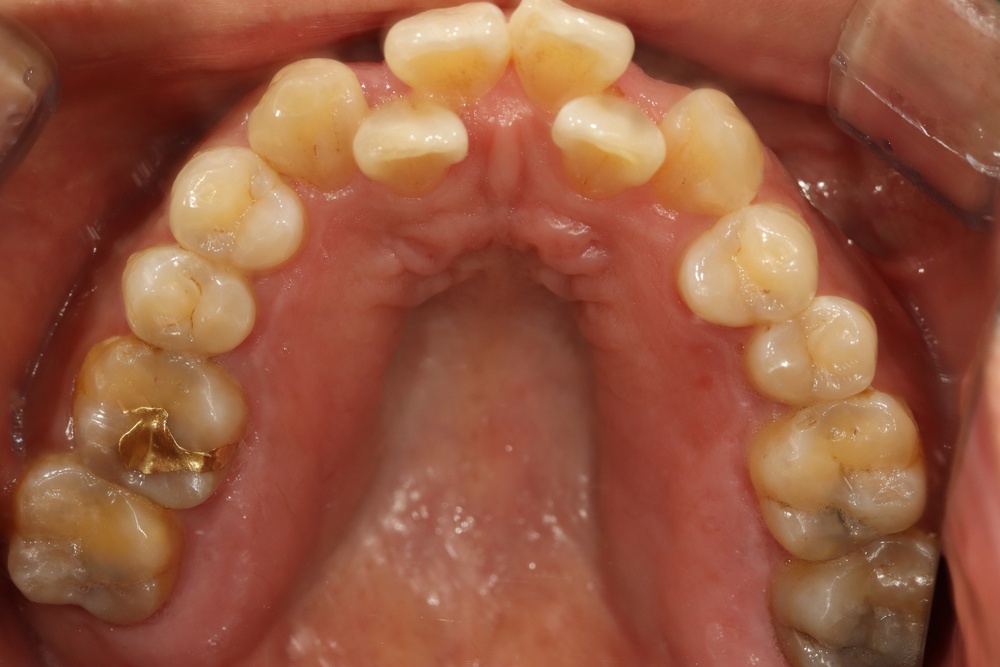

충치가 많아서 교정 전 충치치료를 전반적으로 시행하고, 잇몸치료도 진행하였습니다.

중년기 교정에서 발생가능한 문제점(치아 사이 틈 발생가능성, 잇몸질환)충분히 설명드리고 시작하였습니다.

치아 배열이 거의 완성된 상태로 치료 전 말씀드렸던 치아사이의 틈(블랙트라이앵글)이 있습니다.

환자분과 상의 후 위쪽은 벌어진 공간을 레진으로 메꾸기로 하였습니다.

치아가 가지런해졌고, 윗니 치아 사이의 틈도 메꿔졌으며, 치아에 있던 충치도 모두 치료하였습니다.